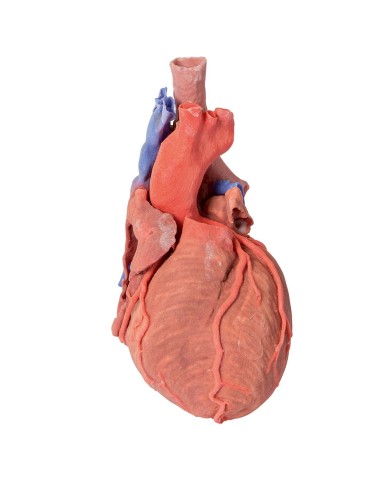

Modello di cuore di alta qualità scomponibile in 5 parti

Modello di cuore di alta qualità scomponibile in 5 parti

Realizzato in stampa 3D ad elevatissima risoluzione a colori.